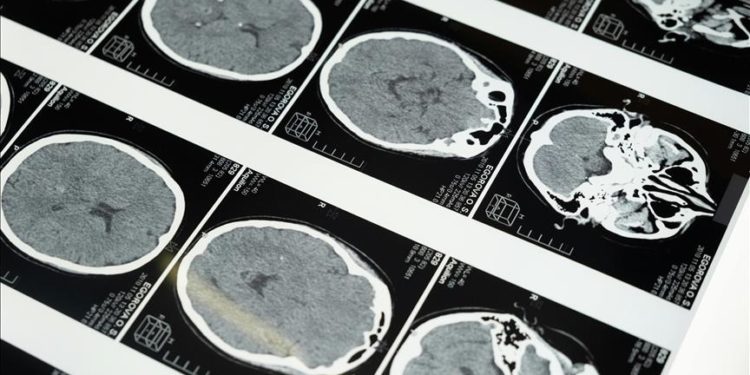

Yeni yapay zeka yazılımıyla inmenin geçirilme zamanı 2 kat daha doğru belirlenebiliyor